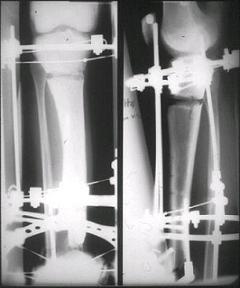

[Ortho] Открытый перелом голени, некроз кожного лоскута

Вложение не в текстовом формате было извлечено…

Имя     : #8.jpg

Тип     : image/jpeg

Размер  : 19588 байтов

Url     : http://weborto.net:8080/pipermail/ortho/attachments/20080506/962ee10e/attachment-0006.jpg